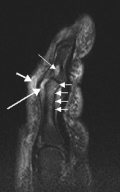

T1 weighted axial MRIs of the fingers in PsA. (a) Pre- and (b) post-contrast showing dactylitis due to flexor tenosynovitis at the second finger with enhancement and thickening of the tendon sheath (large arrow), and synovitis at proximal interphalangeal joint (small arrow). -